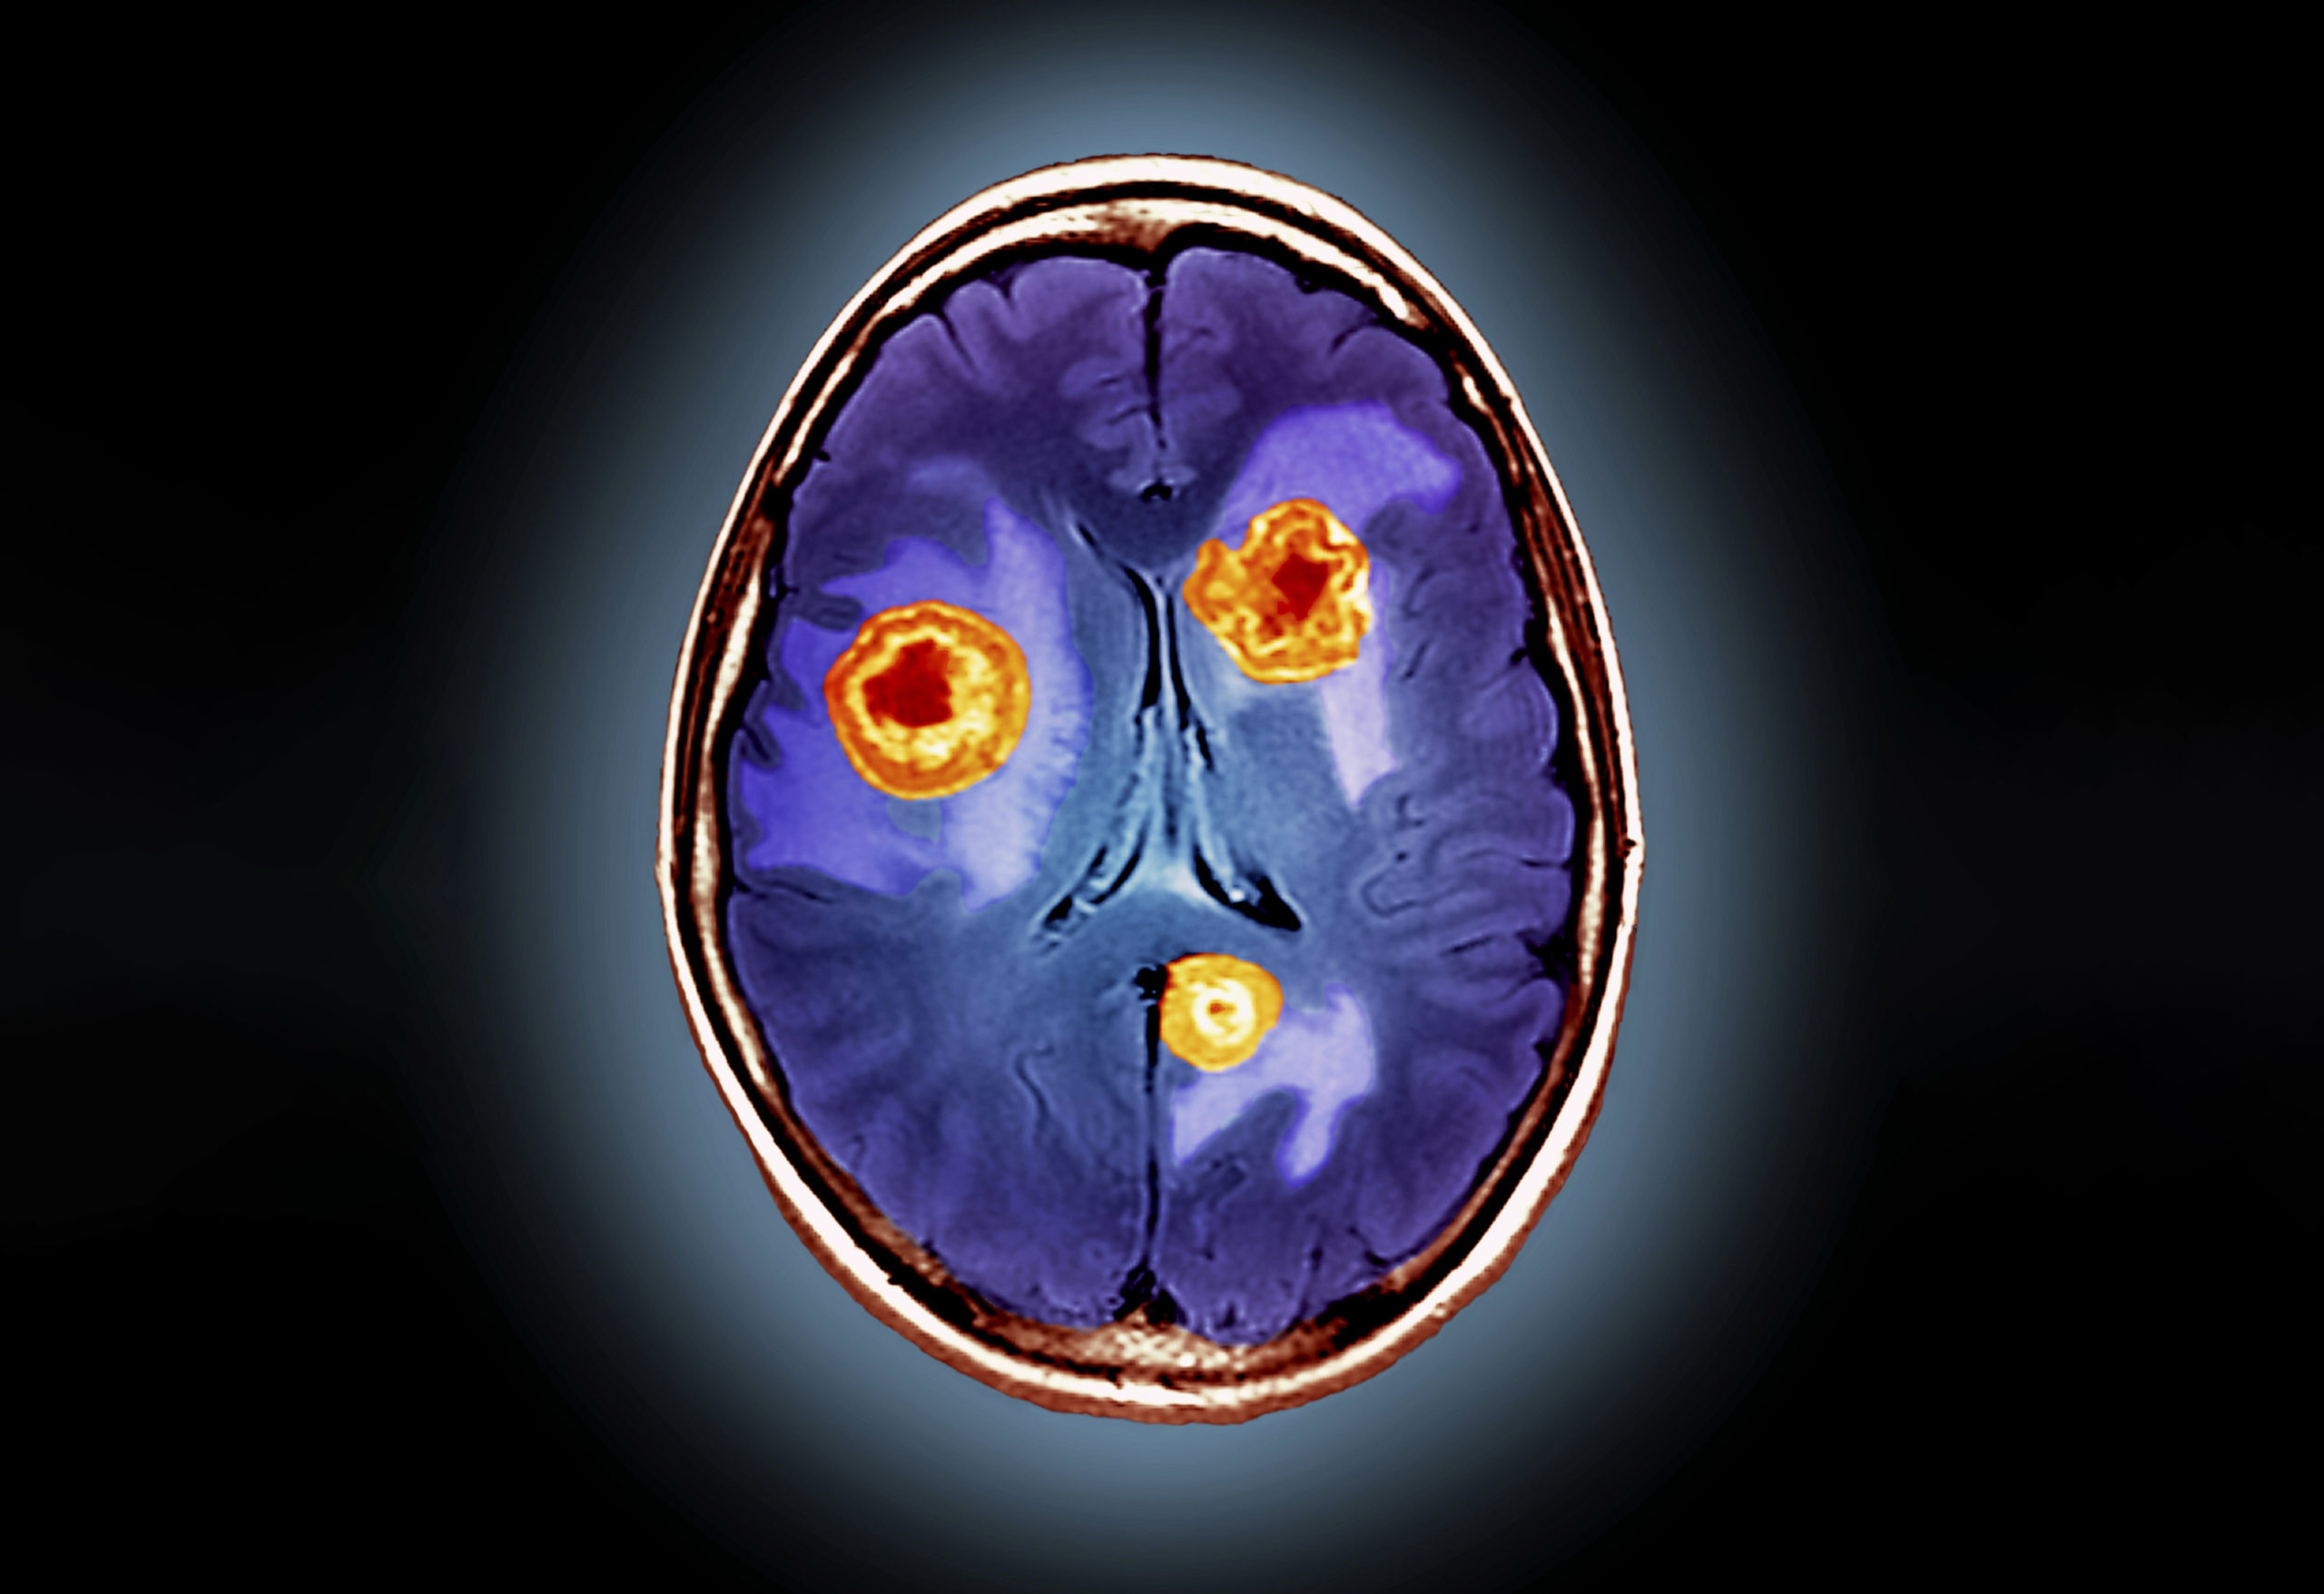

영상 및 진단 검사

뇌종양 진단을 위한 검사에는 CT, MRI 검사, PET검사, 요추천자, 생검 등이 실시될 수 있습니다. CT촬영은 X선 빔을 사용하여 신체 내부의 여러 사진을 찍습니다. MRI 스캔은 자기와 전파를 사용하여 신체의 상세한 단면 사진을 생성합니다. PET(양전자방출단층촬영)스캔은 소량의 방사성 용액을 주입해야 합니다. 암세포는 다른 세포보다 용액을 더 빨리 흡수하므로 이 스캔에서 더 밝게 나타납니다. 요추천자(척수 천자)는 뇌척수액(뇌와 척수 주변의 체액) 샘플을 수집합니다. 외과적 생검은 검사를 위해 마취 하에 종양 조직의 작은 조각을 제거하는 경우입니다.